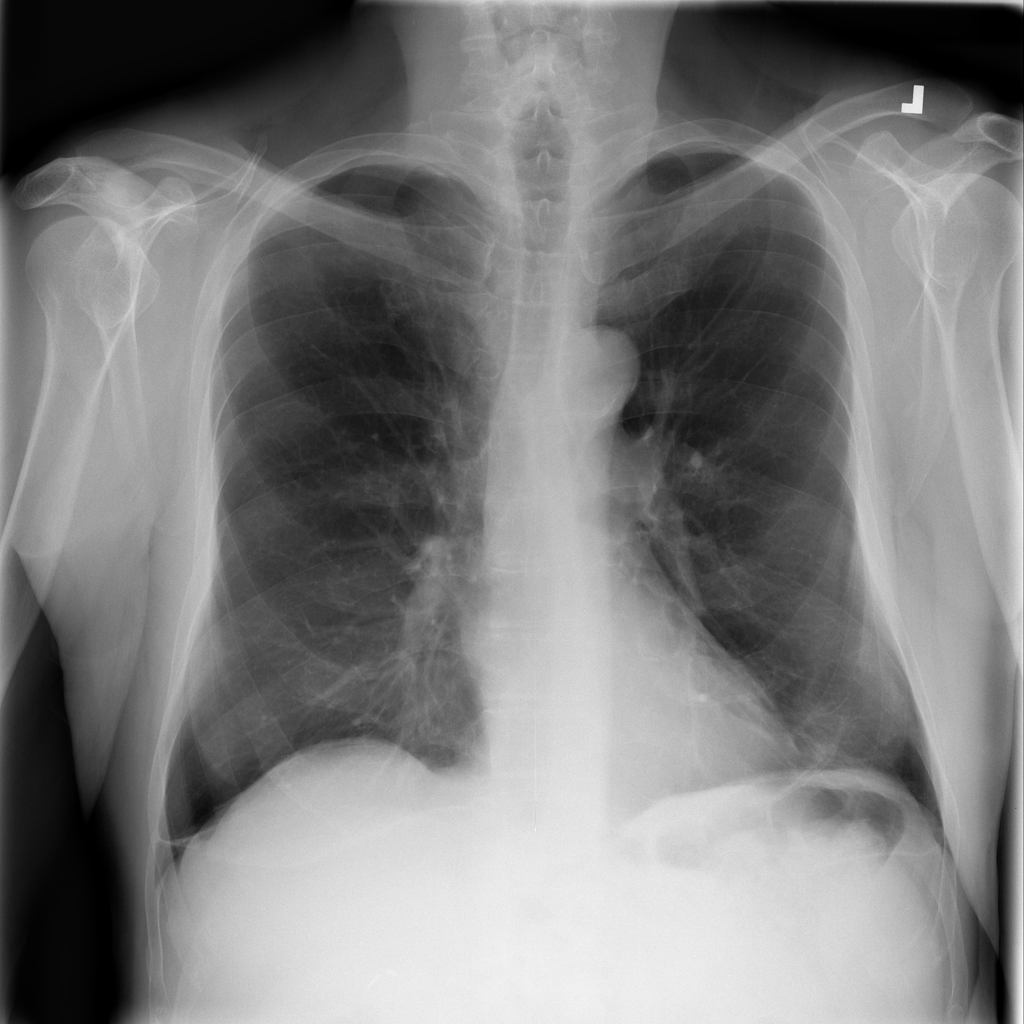

PAT-86C8 · IMG-006Atelectasis

PAT-86C8 · IMG-006

PA